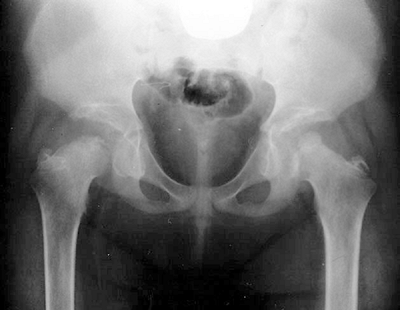

Rhizomelic shortening of the extremities (humerus and femur) (Fig. 15-4)

Radiographs in older children and adults

often reveal increased lumbar lordosis with short pedicles and a

decreased interpedicular distance, know as “champagne glass” pelvis

(width > depth). -

![]() |

|

Figure 15-3 Classification of skeletal dysplasias.

Figure 15-4

Radiograph of 10-year-old girl with achondroplasia. Note features of rhizomelic shortening of the upper extremity. (From Baitner AC, Maurer SG, Gruen MB, et al. The genetic basis of the osteochondrodysplasias. J Pediatr Orthop 2000;20:594–605.) |